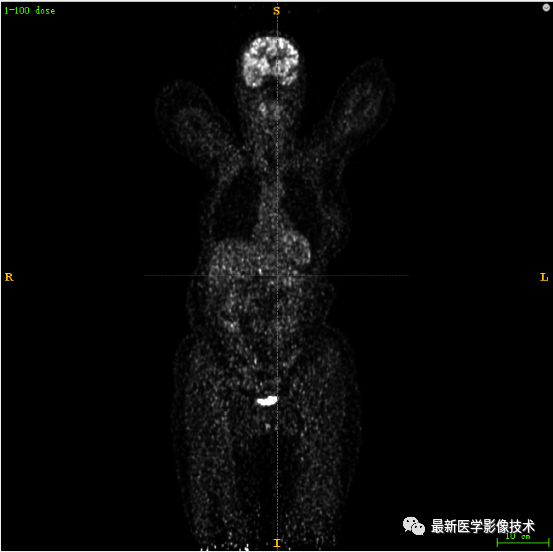

7.3、低剂量10重建结果

第一张是低剂量10的PET图像,第二张是full剂量PET图像,第三张是网络重建的PET图像。